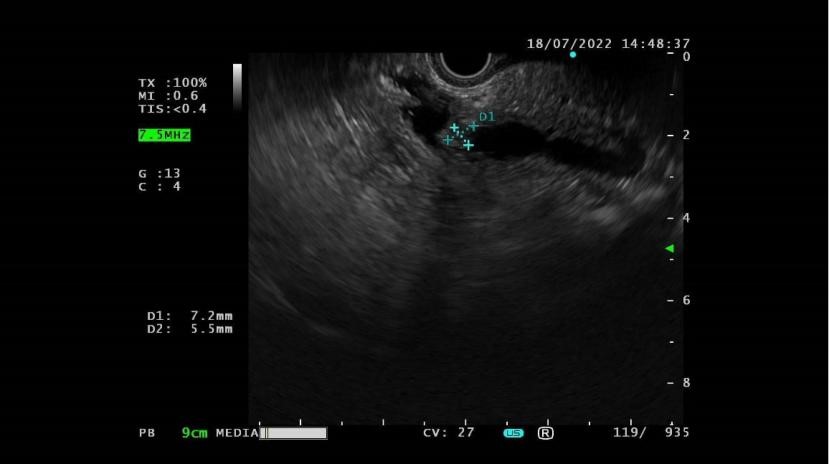

随后戴先生经多方打听,找到了我院肝胆胰外科专家卢杏生主任。主任经过详细了解病情后决定复查增强MRI检查,仍然未能明确是否存在肿瘤可能。但胰管轻微扩张是早期壶腹周围肿瘤(包括胆管癌、胰腺癌、壶腹部癌)的间接征象,不能轻易忽视。在请我院消化科蒋彩凤主任会诊后,决定给戴先生进行超声内镜检查。超声内镜是将内镜和超声相结合的消化道检查技术,超声探头可紧贴胃壁或十二指肠壁进行扫描,与胰腺、胆道仅一壁之隔,可清晰的显示全部胰腺组织、胆管全长及胆囊,对于发现胰腺、胆管末端或十二指肠乳头部的微小肿瘤有不可替代的作用。最终蒋彩凤主任通过超声内镜发现壶腹部一个直径约0.5cm肿瘤,至此终于明确了戴先生的诊断为壶腹部肿瘤,随即制定治疗方案。

(术前超声内镜)